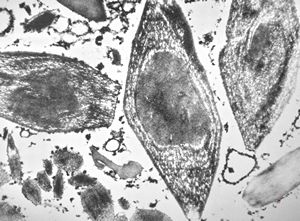

M,15y. | eosinophilic granuloma

M,15y. | eosinophilic granuloma - Langerhans cell

eosinophilic granuloma - Langerhans cell